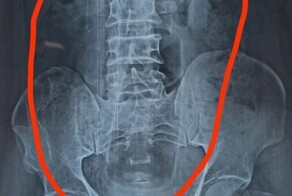

Рентгеновские снимки, сделанные перед операцией в больнице сэра Ганга Рама, показали, что в кишечнике образовались металлические сгустки. 26-летний атлет несколько недель "восполнял" дефицит цинка подручными средствами, когда проходил лечение от психиатрического заболевания, которое не раскрывается.

Пациент поступил в больницу с жалобами на боли в животе и рвоту, которые продолжались более 20 дней.

Монеты и магниты вызвали кишечную непроходимость, на стенках кишечника развилась эрозия. Мужчину экстренно прооперировали.

Извлечённые магниты имели форму сердца, сферы, пули, треугольника и звезды. Послеоперационный рентген подтвердил, что все инородные предметы удалены.